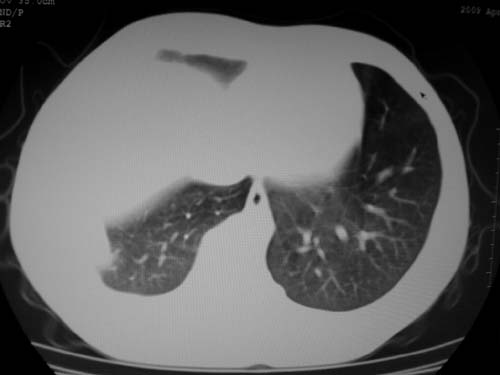

标题: CT19540: 31岁。自述结核性胸水治疗两个月后,在外院拍x线发 [打印本页]

标题: CT19540: 31岁。自述结核性胸水治疗两个月后,在外院拍x线发

右侧胸壁结节状软组织影伴相应肺叶内受侵,伴右侧胸腔积液。考虑:结核性可能大。

支持 右侧胸壁结节状软组织影伴相应肺叶内受侵,伴右侧胸腔积液。考虑:结核性可能大。

右侧胸壁结节状软组织影伴相应肺叶内受侵,伴右侧胸腔积液,结合临床,首先考虑结核。

1)考虑右侧结核性胸膜结节。2)右侧胸膜增厚+包裹性胸腔积液。